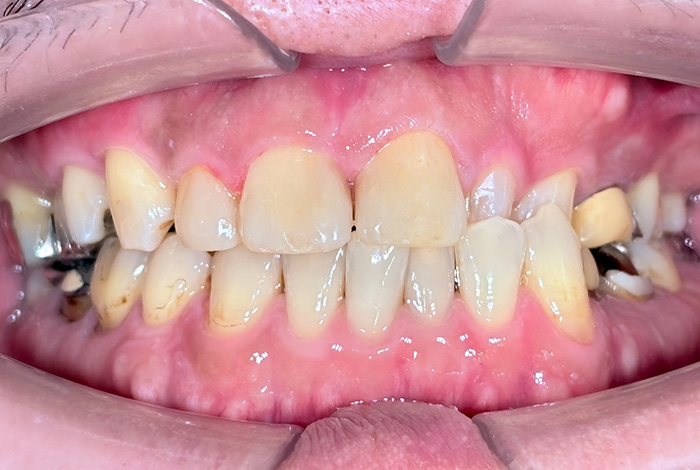

Before

After

患者様は、奥歯でしっかり噛めないことと、前歯の歯並びの乱れを気にされ来院されました。診査の結果、前歯部の叢生(歯並びの乱れ)と、臼歯部の離開咬合(奥歯がしっかり噛み合っていない状態)が認められました。また、臼歯部には古い金属修復物が装着されており、機能面だけでなく審美面においても改善が必要な状態でした。

【治療後】

前歯の歯並びが整い、見た目の改善が認められました。また、奥歯でしっかり噛める状態となり、咬合機能の回復が得られています。

【治療のポイント】

本症例では、歯並びの改善だけでなく、噛み合わせの回復と審美性の向上を同時に行っています。当院は一般歯科と矯正治療の両方に対応しているため、矯正治療後に別の医療機関で補綴治療を行う必要がなく、一貫した治療計画のもとで治療を完結することが可能です。また、奥歯の噛み合わせを矯正治療のみで改善する場合、治療期間が長くなることがありますが、本症例では補綴治療(アンレー)を併用することで、比較的短期間で咬合の改善を行いました。さらに、古い金属修復物をジルコニアに置き換えることで、見た目の改善と機能性の両立を図っています。